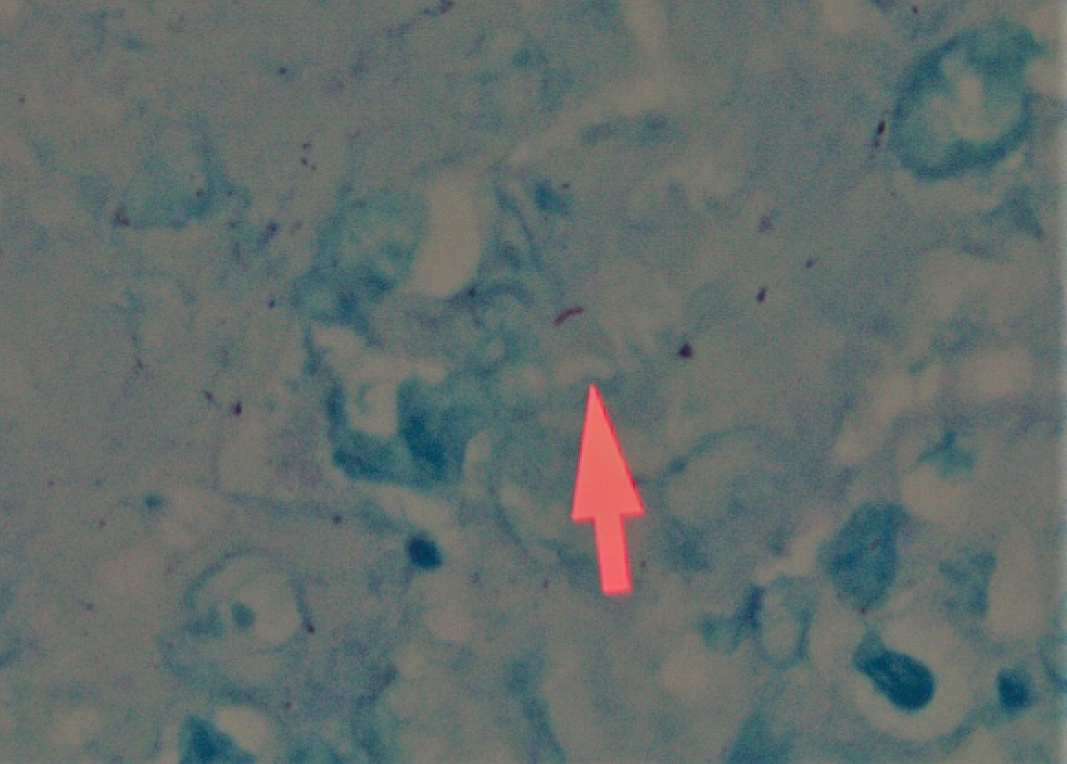

On altı yaşındaki kadın hasta sık tonsillit geçirme ve kronik bir boğaz ağrısı şikayetiyle kliniğimize başvurdu. Hastanın fizik muayenesinde tonsiller bilateral simetrik grade 4 hipertrofik, yapılan endoskopik nazofarinks ve larienks muayenesi ise doğal izlendi. Tonsil yüzeyinde herhangi bir ülsere alan ya da patolojik bir görünüm mevcut değildi. Hastanın son iki yıldır yılda 8-9 kez geçirdiği tonsillit atakları ve çok sık yaşadığı boğaz ağrısı dışında ek bir şikayeti, ek bir hastalığı ya da ilaç kullanım öyküsü yoktu. Fakat hastamız ailesiyle değil bir öğrenci yurdunda kalmaktaydı. Preoperatif dönemde yapılan rutin biyokimya ve hemogram tetkiklerinde herhangi bir anomali izlenmedi. Çekilen posteroanterior (PA) akciğer grafisi normal olarak yorumlandı. Sedimantasyon 10 mm/1.saat, CRP 3.11 mg/lt, beyaz küre (WBC) sayısı 6.6 hücre/mm3, hemoglobin (Hgb) 12.5 gr/dl idi. Hastaya genel anestezi altında tonsillektomi operasyonu yapıldı. Tonsil dokuları kolaylıkla diseke edilerek çıkartıldı. Kliniğimizde rutin bir uygulama olarak çıkarılan tonsil dokuları patolojik incelemeye gönderildi. İki hafta sonra patoloji sonucu kazeifiye granülamatöz tonsillit olarak raporlandı. Bunun üzerine hasta İnfeksiyon Hastalıkları ve Klinik Mikrobiyoloji Anabilim Dalı tarafından değerlendirildi. Serolojik testlerde anti-Toxoplasma IgM ve G negatif, anti-CMV IgM negatif, anti-CMV IgG pozitif, anti-HIV negatif, syphilis ELISA negatif, Brucella aglütinasyon testi negatif olarak sonuçlandı. Uygun materyal olmaması nedeniyle tonsil dokusunda tüberküloz kültürü ve balgamda “aside dirençli bakteri (ARB)” boyama ve kültürü yapılamadı. Tüberkülin deri testi 20 mm ve tonsil dokularından yapılan Ziehl-Neelsen boyamasında iki alanda pozitif boyanan birer tüberküloz basili saptandı (Resim 1 ve 2). Akciğer, larinks ve diğer organ incelemelerinde tüberküloz tespit edilmedi.